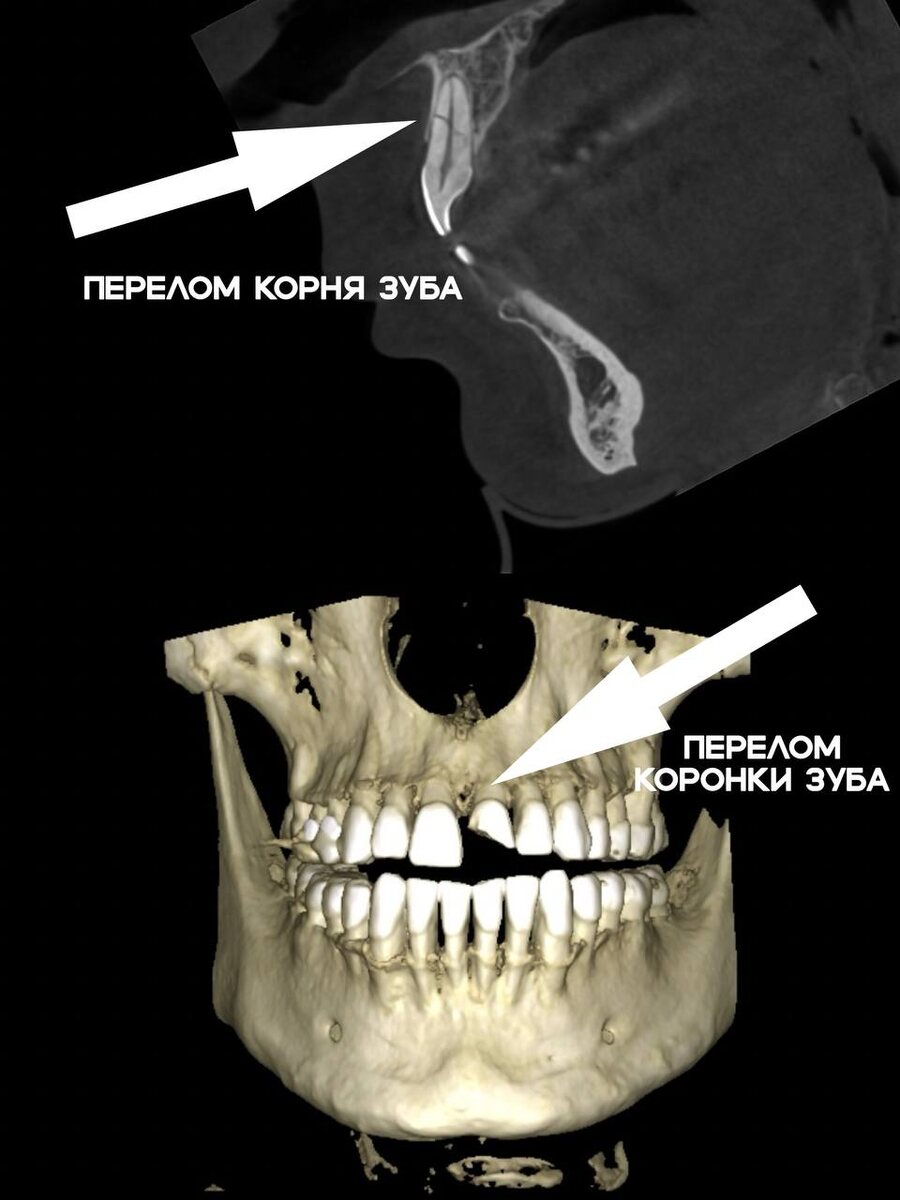

Клинический случай из практики:

Летом в нашу клинику обратился пациент после падения с электросамоката. Итог неосторожной поездки оказался весьма печальным:

• У центрального резца сломана коронка: Зуб был сколот почти на половину, что потребовало удаления нерва (эндодонтическое лечение) и последующего восстановления с помощью коронки.

• У второго центрального резца — перелом корня: Такой перелом не поддаётся восстановлению, и зуб пришлось удалить полностью.

В результате пациент потерял один зуб, а второй — восстановил только с помощью сложного и дорогостоящего лечения. Всё это — из-за одного неудачного падения на высокой скорости.